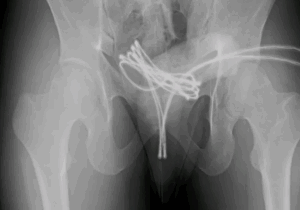

Acabó en urgencias tras meter un cable USB por su uretra para «obtener placer sexual»

Lapatilla junio 11 2025, 1:18 pm Los escáneres mostraron que el cable había sido introducido en su vejiga. Crédito: Cureus Un ... Leer más